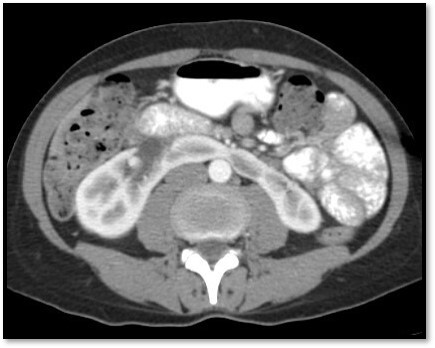

Q

What pathology is seen here?

A

Unilateral Renal Agenesis